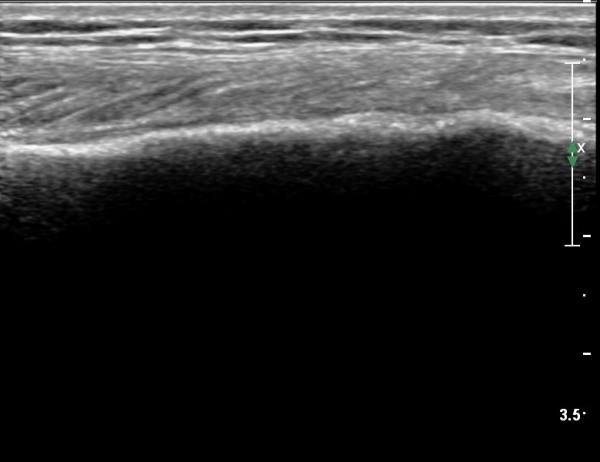

[¹«¸­] °æ°ñ ÇǷΰñÀý ÃÊÀ½ÆÄ¼Ò°ß(sonographic findings of stress fracture of tibia)

ÃÊÀ½ÆÄ °Ë»ç

¹Ì¼¼ÇÏ°Ô ¿¬ºÎÁ¶Á÷ ºÎÁ¾°ú °¡°ñ Çü¼ºÀÌ °üÂûµÊ.

Bilateral stress fracture of the tibia diagnosed by ultrasound. A case report